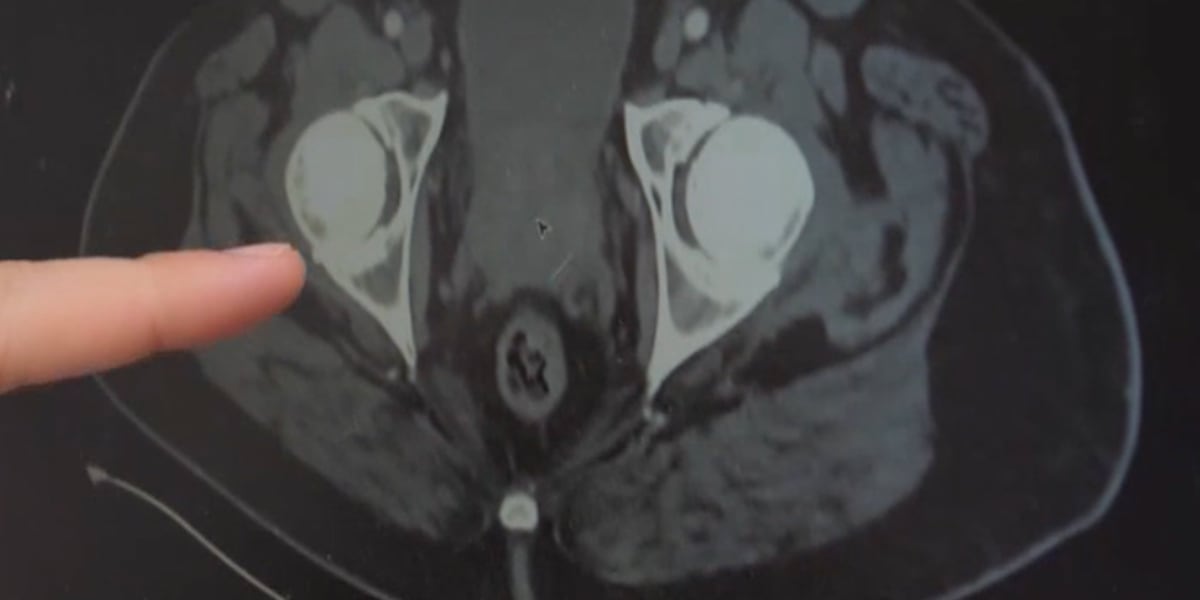

MU Healthcare’s Meg Judy shows us a laser surgery that can help correct an enlarged prostate.